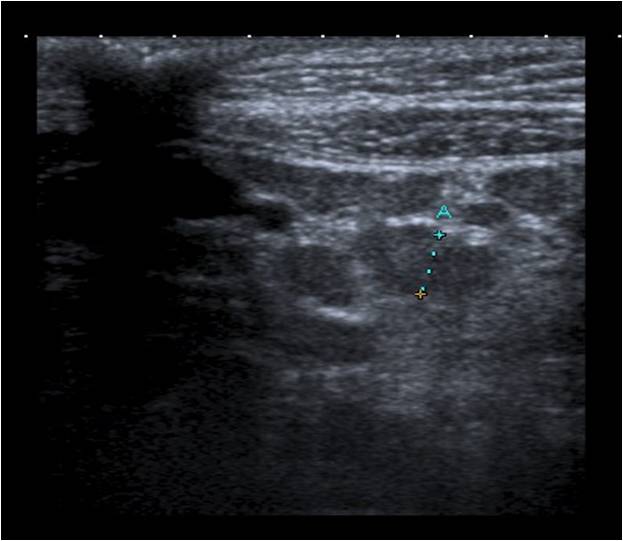

Se repite la ecografía abdominal: múltiples adenopatías de aspecto inespecífico en el área mesentérica con una discreta cantidad de líquido libre en fosa ilíaca derecha (FID).

Impresión diagnóstica: adenopatías mesentéricas reactivas.